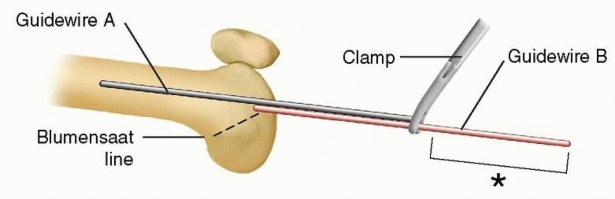

Retrograde femoral nailing can be defined as any femoral nailing technique with a distal entry from the condyles or through an intercondylar, intra-articular starting point. For this chapter,retrograde femoral nailing will refer to nails with an intercondylar starting point that extend through the shaft region to the proximal femur. In certain fracture situations, shortened nails (supracondylar nails) can be used with the same starting point for fixation of distal femoral fractures. ## ANATOMY The femoral shaft is tubular in shape over the extent of the isthmus, gradually flaring infraisthmally into the distal femur, which is trapezoidal in cross-section. The entry point for the retrograde femoral nail is located at the distal end of the patellofemoral grove, just anterior to the posterior cruciate ligament insertion ( FIG 1A). Radiographically, this is located in the midline or just medial to the midline between the condyles on the anteroposterior (AP) view and laterally just anterior to the line of Blumensaat as it meets the trochlear grove ( FIG 1B,C).5, 12, 14, 15, 18 This flat articular area has minimal to no contact with the patella until 120 degrees of flexion. 1, 5  ---

---  ### FIG 1 • A. Distal femur viewed end on, with ideal starting point for retrograde femoral nailing identified (asterisk) just anterior to the posterior cruciate ligament insertion. B,C. AP and lateral radiographs of the knee, with the initial starting guidewire positioned at the ideal starting point for retrograde femoral nailing. The radiographic landmark for the trochlear groove (TG) is indicated on the AP radiograph and for the line of Blumensaat (BL) on the lateral radiograph. Pertinent proximal anatomy includes neurovascular structures anterior to the proximal femur, close to interlocking screw insertion sites. 24 The femoral artery is medial to the proximal femur, with branches that cross the anterior femur more than 4 cm distal to the lesser trochanter. Branches of the femoral nerve cross more proximal starting 4 cm distal to the piriformis fossa. Damage to neurovascular structures caused by proximal locking screw insertion can be avoided or minimized by avoiding medial dissection and with placement at or above the lesser trochanter ( FIG 2). ## PATHOGENESIS Femoral shaft fractures are markers of high-energy injuries. 10, 12, 13, 14, 23, 27 Studies have shown that 38% of trauma patients diagnosed with a femoral shaft fracture have additional injuries. 3, 7, 8, 26 In femur fracture patients with associated injuries, the most common findings are other musculoskeletal injuries (93%), thoracic injuries (62%), head injuries (59%), abdominal injuries (35%), and facial injuries (16%). 7

### FIG 1 • A. Distal femur viewed end on, with ideal starting point for retrograde femoral nailing identified (asterisk) just anterior to the posterior cruciate ligament insertion. B,C. AP and lateral radiographs of the knee, with the initial starting guidewire positioned at the ideal starting point for retrograde femoral nailing. The radiographic landmark for the trochlear groove (TG) is indicated on the AP radiograph and for the line of Blumensaat (BL) on the lateral radiograph. Pertinent proximal anatomy includes neurovascular structures anterior to the proximal femur, close to interlocking screw insertion sites. 24 The femoral artery is medial to the proximal femur, with branches that cross the anterior femur more than 4 cm distal to the lesser trochanter. Branches of the femoral nerve cross more proximal starting 4 cm distal to the piriformis fossa. Damage to neurovascular structures caused by proximal locking screw insertion can be avoided or minimized by avoiding medial dissection and with placement at or above the lesser trochanter ( FIG 2). ## PATHOGENESIS Femoral shaft fractures are markers of high-energy injuries. 10, 12, 13, 14, 23, 27 Studies have shown that 38% of trauma patients diagnosed with a femoral shaft fracture have additional injuries. 3, 7, 8, 26 In femur fracture patients with associated injuries, the most common findings are other musculoskeletal injuries (93%), thoracic injuries (62%), head injuries (59%), abdominal injuries (35%), and facial injuries (16%). 7  ---

Intraoperative fluoroscopy is used to obtain a perfect lateral of the knee. The line of Blumensaat should be clearly identified (see FIG 1C). A radiopaque guidewire can be used to identify the center of the long axis of the femur in order to determine the correct level of the skin incision. The guide pin is used to center a 1.5- to 2.5-cm incision just medial to the midline. A medial flap is created using subcutaneous dissection. A medial peritendinous arthrotomy is then made to allow entrance of the initial starting guidewire into the intracondylar notch. ## TECHNIQUES

1. ## Placing the Guidewire The surgeon confirms the correct placement of the initial starting guidewire on the AP and lateral fluoroscopic radiographs. On the lateral image, the initial starting guidewire should be situated at the apex of the line of Blumensaat, in line with the femoral shaft (see FIG 1C). On the AP image, the guidewire should be centered or just medial to the midline in the trochlear groove, in line with the femoral shaft (see FIG 1B). On the AP image, the fluoroscope is moved proximally to be certain the guidewire is directed at the center of the canal. When starting to drill the initial guidewire, the surgeon's hand should drop slightly to prevent the wire from falling into the posterior cruciate ligament insertion; the hand is raised once the wire enters the cortex, so as to be in line with the femoral shaft. Once the initial starting guidewire is centered on the AP and lateral images, the wire is passed into the distal femoral shaft. A soft tissue retractor is placed over the initial starting guidewire to protect the patellar tendon during reaming. 2. ## Creating and Reaming the Starting Hole The initial starting reamer is used to create the starting hole. (Alternatively, an awl or a step drill can be used to make the starting hole using the principles described earlier.) Once the starting hole has been made, a beaded-tip guidewire is passed to the level of the fracture. 3. ## Fracture Reduction Traction is used to restore length. The surgeon must ensure that adequate anesthesia (full paralysis) is employed. There are many deforming muscle forces, depending on the level of the fracture. If the fracture cannot be reduced by manual traction, use of bumps, pulling with sheets wrapped around the proximal or distal thigh, or pushing with mallets are some options. The abductor muscles will abduct and externally rotate the proximal femur after high subtrochanteric and proximal shaft fractures. Inserting a unicortical 5-mm Schanz pin through a percutaneous incision in the lateral cortex just above the fracture or in the greater trochanter can gain excellent control of the proximal fracture fragment. The iliopsoas muscle will flex and internally rotate proximalthird femoral shaft fractures by its pull on the lesser trochanter. Again, inserting a unicortical 5-mm Schanz pin through a percutaneous incision in the lateral cortex just above the fracture or in the greater trochanter can gain excellent control of the proximal fracture fragment. The adductor muscles span most shaft fractures and exert a strong axial and adduction force. Sometimes, midshaft transverse fractures can be the most difficult to reduce. Inserting a unicortical 5-mm Schanz pin through a percutaneous incision in the lateral cortex just above and just below the fracture can gain excellent control of the proximal and distal fracture fragments. Distal fractures tend to angulate into recurvatum through the pull of the gastrocnemius muscle. Bumps placed under the knee to flex the knee can help relax the gastrocnemius muscle. One can also use blocking screws in distal fractures to surgically create a narrow “canal” in the metaphyseal region in line with the canal of the femoral shaft so that the intramedullary nail can help with reduction of the fracture. Alternatively, a femoral distractor can assist with obtaining and maintaining fracture reduction for a fracture at any level. It can be placed laterally, inserted proximally at the greater trochanter, and distally in either the posterior aspect of the femoral condyle or in the proximal tibia. Alternatively, some surgeons recommend anterior placement to avoid potential posterior angulation of distal fracture patterns. Lastly, some fractures require opening of the fracture site to obtain reduction, with the finding of the muscle interposed within the fracture. We recommend laterally based incisions unless otherwise dictated by an open fracture wound. Restoration of length and correct rotation can be assessed clinically as well as radiographically by closely scrutinizing the diameter of the medial and lateral femoral cortex, ensuring they are of equal diameter proximal and distal to the fracture. 4. ## Passing the Guidewire

Once the fracture is reduced on the AP and lateral images, the surgeon passes the guidewire to end just below the level of the piriformis fossa. This is done to ensure that reaming is performed past the level of the lesser trochanter because the reamers stop at the beaded portion of the guidewire. 5. ## Reaming Reaming should begin with an end-cutting reamer (typically size 8 mm or 9 mm in diameter). Fracture reduction must be maintained throughout the reaming process to minimize eccentric reaming. Reaming should be performed slowly and in 0.5-mm increments to prevent thermal necrosis. The approximate nail diameter is selected based on the preoperative measurement of the femoral isthmus. The final nail diameter should be selected based on the size of the reamer that provides the initial cortical chatter. The canal is reamed to 1.0 to 1.5 mm over the selected nail diameter. Nail length can be determined multiple ways: A radiolucent ruler can be placed on the anterior aspect of the femur. The nail should end above the level of the lesser trochanter on the AP radiograph and should be measured so that it is deep to the apex of the line of Blumensaat on the lateral view (see FIG 1C).  --- TECH FIG 1 • Schematic diagram of a lateral view of the knee, obtaining femoral length measurement using the twoguidewire technique. The amount of guidewire B (asterisk) indicated by the bracket equals the amount of guidewire A in the femoral canal. Alternatively, a second guidewire of the same length can be inserted into the knee to end just deep to the apex of the line of Blumensaat on the lateral fluoroscopic image. This additional guidewire is clamped at the level of the guidewire already in place. The portion distal to the guidewire in place is measured to equal the amount of guidewire in the femoral canal ( TECH FIG 1). In addition, many nailing systems have system-specific measurement guides that are outlined in their technique manuals. If the measurement is between nail sizes, the shorter nail is selected. Length can be added with an end cap if required. 6. ## Placing the Nail Once the nail size is selected, the nail is inserted over the guidewire. Most current systems allow the beaded-tip guidewire to pass through the cannulated nail. If an older system is being used, then the beaded-tip guidewire must be exchanged for a smoothtip guidewire using an exchange tube. If guidewire exchange is required, the surgeon ensures correct placement of the smooth-tip guidewire on the AP and lateral images before nail insertion. The nail is inserted over the guidewire and should pass relatively easily. If the nail does not advance easily, the surgeon performs a careful AP and lateral fluoroscopic assessment of the fracture reduction and nail placement. Nail insertion depth is assessed on the lateral knee radiograph. The nail should end proximal to the apex of the line of Blumensaat to ensure subchondral placement ( TECH FIG 2A). The surgeon confirms that fracture length and alignment have been restored on the AP and lateral radiographs. The surgeon confirms that the nail length selected puts the proximal tip of the nail ending at or above the level of the lesser trochanter ( TECH FIG 2B). The nail is advanced if the proximal tip does not end at or above the level of the lesser trochanter. If this leaves the nail countersunk, end caps can be selected to gain nail length. Care must be taken to remain below the piriformis fossa to avoid proximal nail protrusion. The nail is locked distally using the distal interlocking guides. We typically use one lateral to medial distal interlocking screw for transverse midshaft femoral fractures, and a second anterolateral to posteromedial distal interlocking screw for comminuted or distal femoral fractures. Using live fluoroscopy, the fluoroscopic machine is rotated about the knee to assess the length of the interlocking